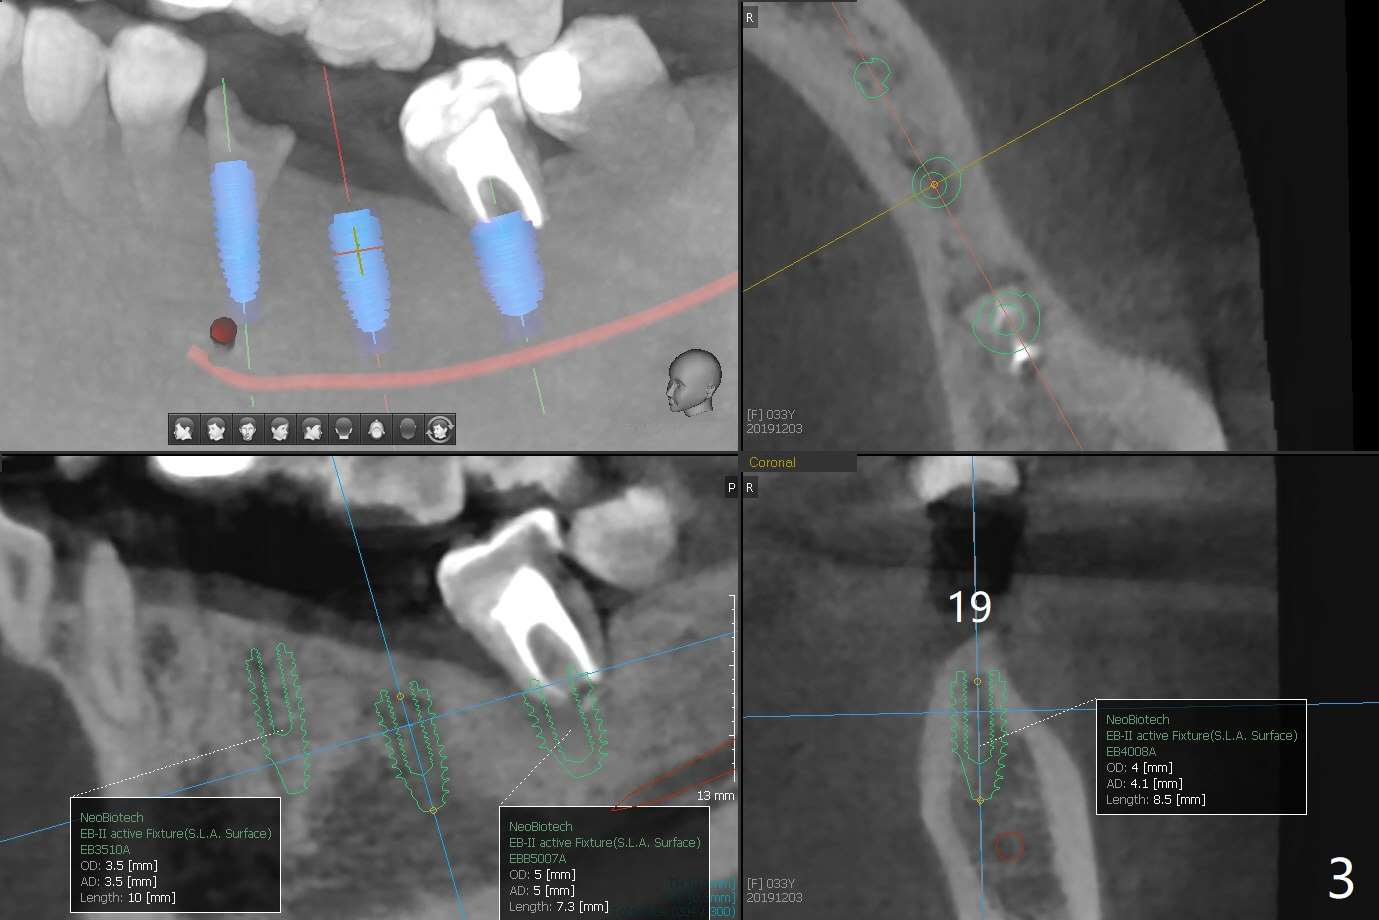

A 33-year-old woman fractures #20 equigingival with caries (Fig.1,2 barely salvageable). The ridge at #19 is atrophic (Fig.3), while the tooth #18 has mobility II (Fig.4). It seems that the best option would be extraction of #18 and 20 and immediate implant with guide (Fig.4). The tooth #20 is vital; socket shield will be conducted. To further prevent buccal plate collapse, a 3.5 or 4.0x10 mm implant will be placed lingual (Fig.2).